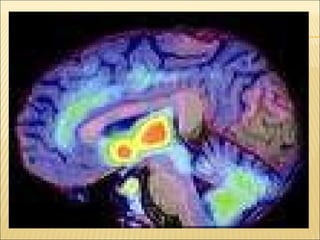

Sistema Límbico : se relaciona con los estados afectivos como miedo, ira, cólera y placer.  Tálamo : Releva los impulsos nerviosos que se dirigen a la corteza cerebral y a otros centros nerviosos del cerebro, y que llegan de los receptores sensitivos, menos el olfato. Hipotálamo :  regula sed, comportamiento sexual, sueño, y coordina la actividad del sistema nervioso y endocrino.

Sistema Límbico :se relaciona con los estados afectivos como miedo, ira, cólera y placer. Tálamo : Releva los impulsos nerviosos que se dirigen a la corteza cerebral y a otros centros nerviosos del cerebro, y que llegan de los receptores sensitivos, menos el olfato. Hipotálamo : regula sed, comportamiento sexual, sueño, y coordina la actividad del sistema nervioso y endocrino.